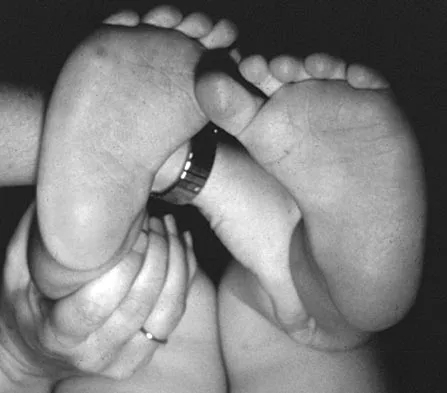

Figure 16 shows the clinical photograph of a 3-month-old infant with a foot deformity that has been nonprogressive since birth. Examination reveals that the deformity corrects actively and with passive manipulation. There is no associated equinus. Management should consist of

Explanation